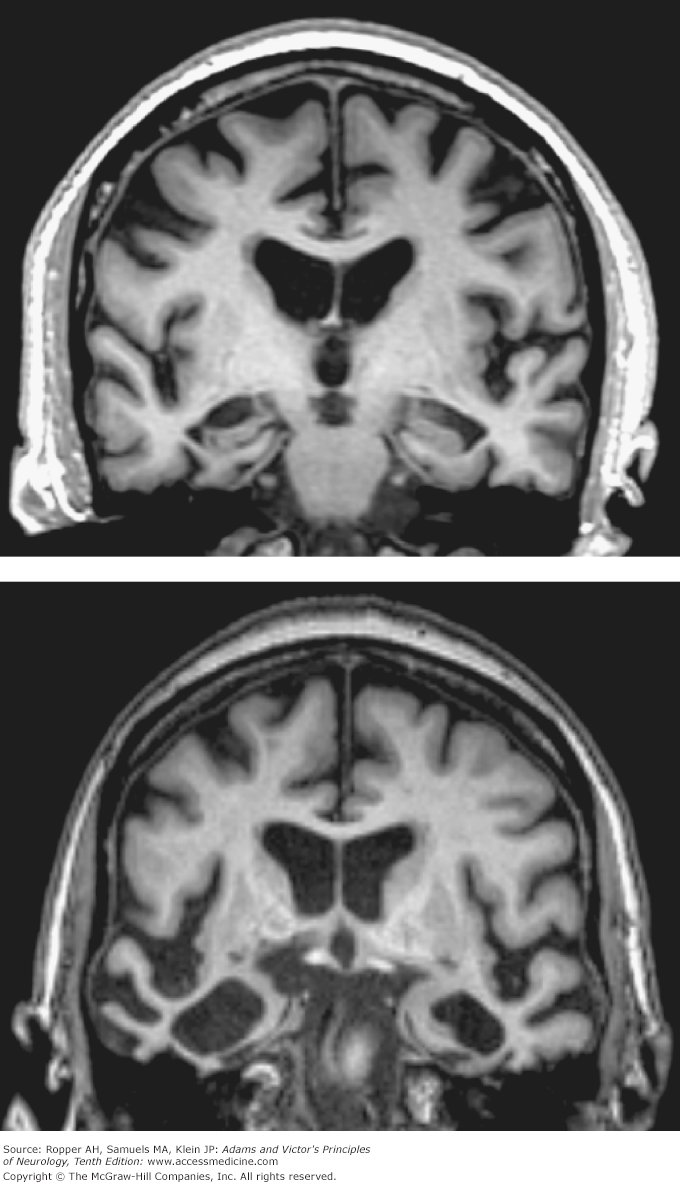

Top Image: Coronal T1-weighted MRI of a 74-year-old man with moderate Alzheimer-type dementia. Diffuse cerebral and hippocampal atrophy with ex vacuo ventricular and cortical sulcal dilation is noted.

Bottom Image: Coronal T1-weighted MRI of a 70-year-old woman with behavioral variant frontotemporal lobar dementia. Atrophy of the right greater than left temporal lobes is out of proportion to atrophy of the frontal and parietal lobes.